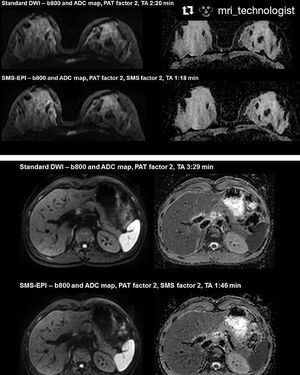

#Repost @mri_technologist (@get_repost) ・・・ Diffusion-weighted imaging (DWI) has great potential in body oncology, however, being a single-shot technology, the acquisition is relatively time consuming. Simultaneous Multi-Slice (SMS)-EPI deploys multiband pulses to excite multiple slices simultaneously. This excitation is combined with a blipped CAIPIRINHA approach during readout to reduce g-factor related SNR loss. As a result, an additional acquisition time reduction of up to 46% without compromising image quality compared to a standard GRAPPA 2 can be achieved with SMS 2 in combination with GRAPPA 2 in breast and abdominal scans. Prerequisite: Software version syngo MR E11C and SMS-EPI license. #MRI #SMS #DWI #SS_EPI #MRI_Technologist #MRITechnologist #MRI_Radiographer #Siemens_MRI